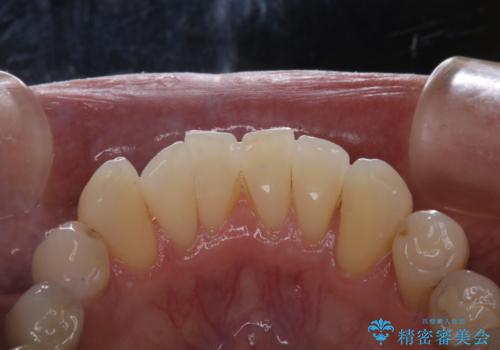

- PMTCでのメンテナンスを定期的に行っている方です。PMTC30分コースを行いました。

日々の磨き残しなどをそのまま放置すると、細菌が固まり硬い歯石になります。

歯石になってしまうと、とても硬く、歯ブラシで取り除くことが出来なくなります。

よって、歯科衛生士による専門的なクリーニングを定期的に行うことがとても大切です。

メンテナンスの間隔は個人差がありますが、基本的には2~3カ月に一度行うことをおすすめしています。